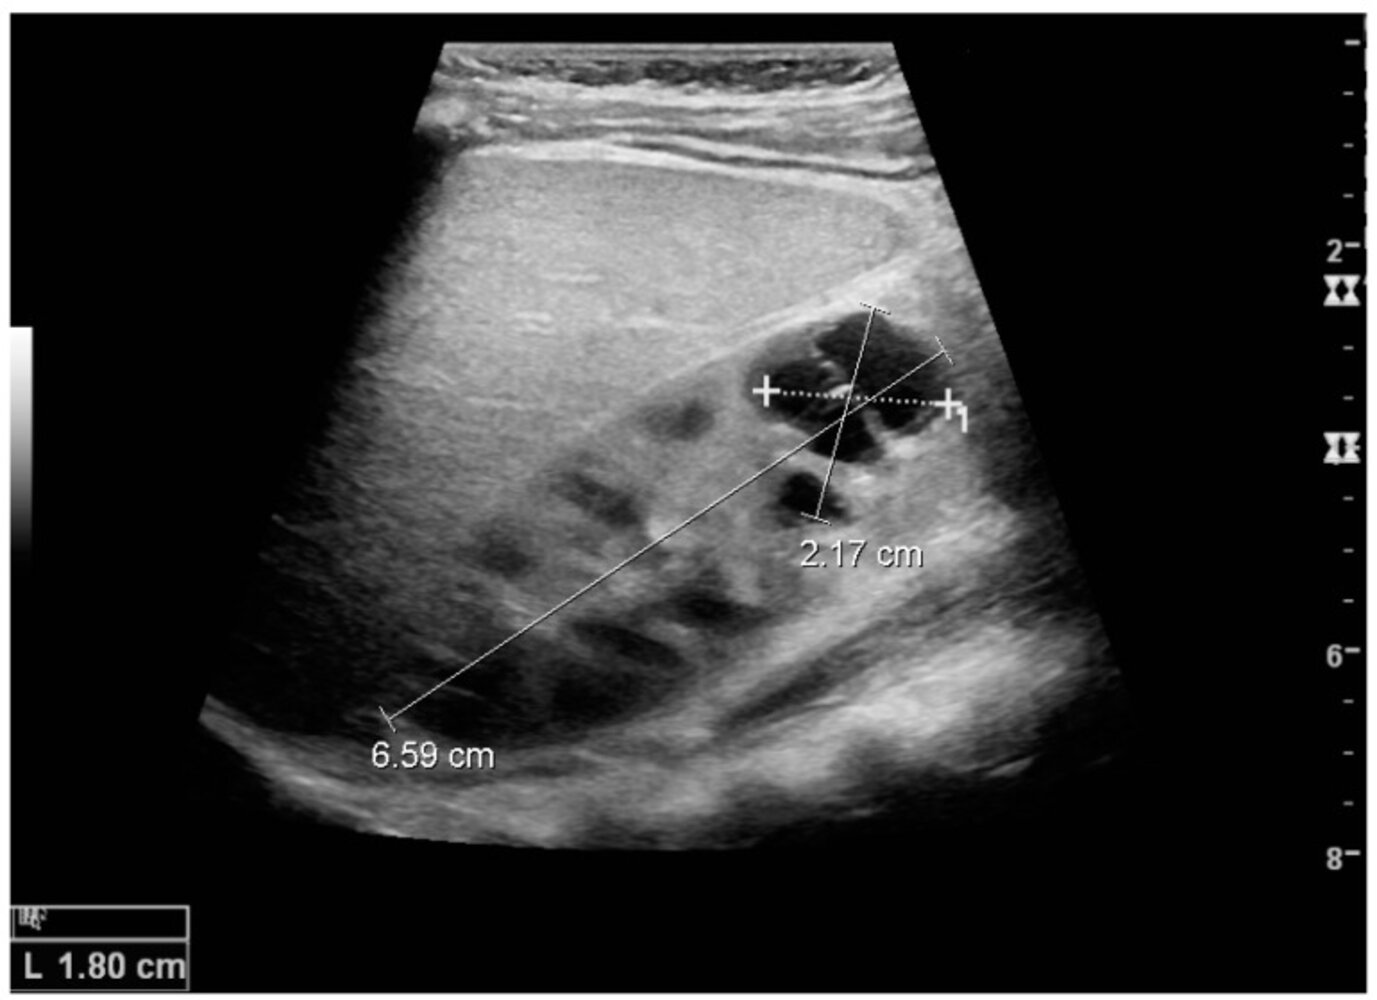

• Round or oval anechoic cysts (filled with ultrafiltrate)

• Dorsal sound amplification

• Minor reduction in sound wave intensity in homogeneous, clear liquids as there is no refraction (i.e., the content of the cyst is anechoic)

• On the dorsal side of the cysts, the undiminished sound wave results in higher contrast compared to the neighboring tissue (i.e., dorsal sound amplification).